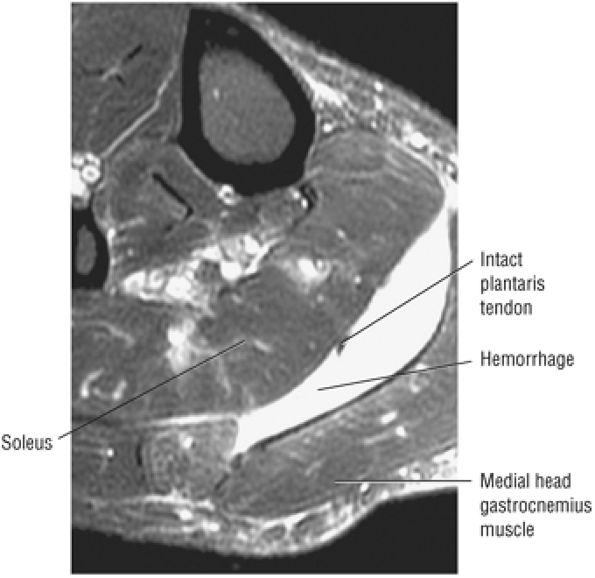

-

Achilles tendon rupture usually occurs 2 to 6 cm proximal to its os calcis insertion.

Sagittal images are used to identify the proximal and distal tendon ends.

Axial FS PD FSE images are used to confirm complete rupture (an intact plantaris may simulate an intact tendon in the sagittal plane).